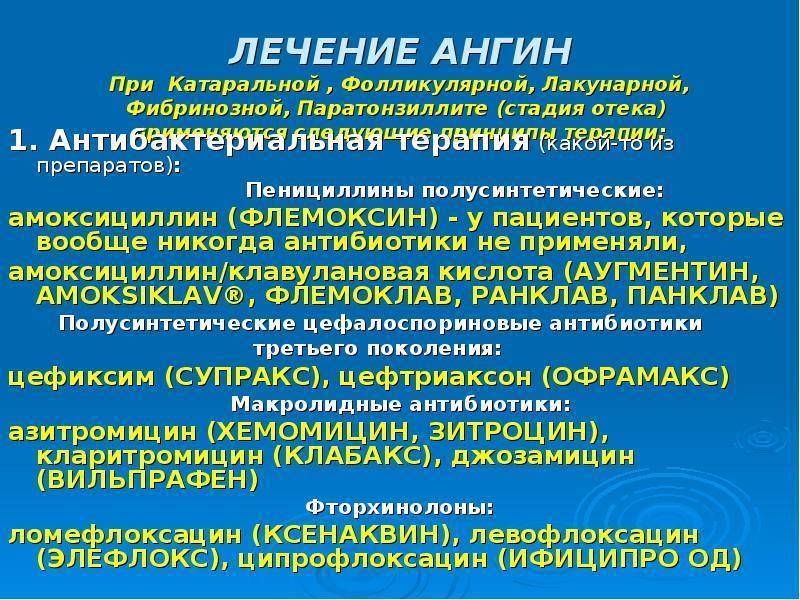

- Прием антибиотиков. Зачастую лечение заболевания проводится в домашних условиях. Обязательным условием терапии являются антибиотики при лакунарной ангине. Они позволяют быстрее восстановиться пациенту и вовремя устранить возбудителя. Длительность лечебного курса составляет от пяти до десяти дней в зависимости от тяжести болезни. Также прием антибиотиков позволяет снизить вероятность возникновения осложнений. Взрослым назначают такие средства, как Сумамед, Азитромицин, Флемоксин Солютаб.

Также в детском возрасте обязательно назначают антибиотики в виде Амоксиклава, аугментина или Флемоксина. Наряду с этим нужно принимать средства, которые нормализуют микрофлору кишечника.